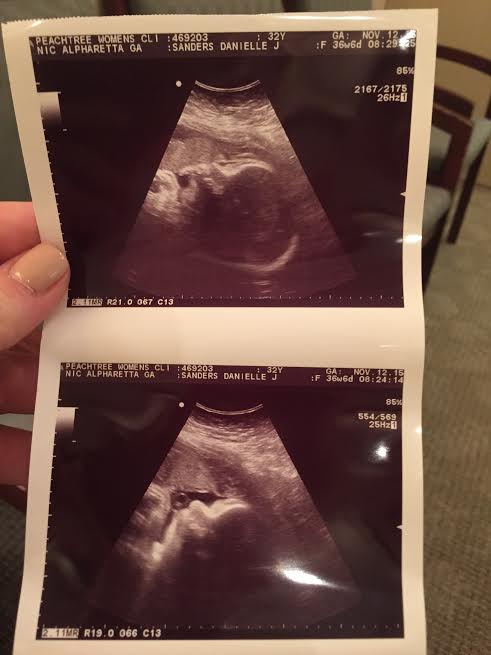

36w6dultrasoundMy appointment went pretty well last week. Blood pressure is still 110/66 and no weight gain!

Baby girl looks amazing. I still can’t wrap my head around loving someone I’ve never met so much. They said she had lots of hair, full lips and is measuring a bit big… They said she’s currently about 7lbs7oz – give or take a pound. The bigger concern is that her head is on the smaller side and her belly is on the bigger side, so they worry about her shoulders getting stuck. (Guess what my dumbass did when I got home? Googled about shoulders getting stuck and how it can cause cerebral palsy.) Anyhow, my midwife said they won’t be actually concerned unless I go the full 40 weeks, and at that point, I’ll have another ultrasound to see her growth and determine what the next steps should be.